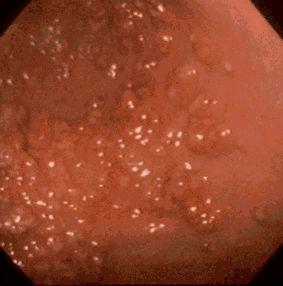

Poliposis juvenil evidenciada en estómago, que acompaña Cáncer Multiple.

[Image-ID:178]

Lesión que asemeja tumoración/Poliposis juvenil

estómago(región)/otros

Endoscopia